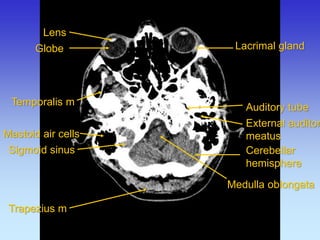

Lens

Globe

Auditory tube

Lacrimal gland

Mastoid air cells

Medulla oblangata

Rectus medialis

Temporalis m

Cerebellar hemisphere

Trapezius m

Sigmoid sinus